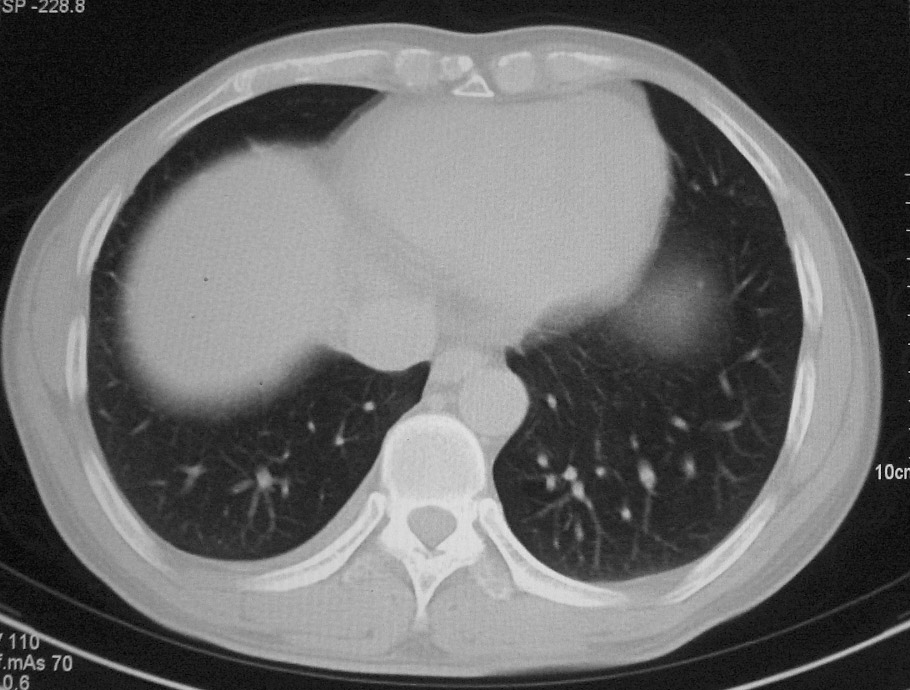

标题: CT5485:[原创]肺部占位请讨论

右上叶支气管肺癌并右上叶阻塞性不张,右侧少量胸腔积液.

右上肺中央性肺癌伴右侧胸腔少量积液!右上肺胸膜下还有一小病灶,不完全排除结核,但个人支持恶性肿瘤!建议早穿刺活检。

右肺上叶中央型肺癌并上叶肺不张、纵隔淋巴结肿大.右侧少量胸腔积液。

右上肺中心型肺癌并肺不张,纵膈淋巴结肿大。右侧少量胸腔积液。

右肺上叶不张,考虑中央型肺癌。右侧胸膜肥厚

右上肺癌,肺不张,纵隔淋巴结肿大

右肺上叶中央型肺癌